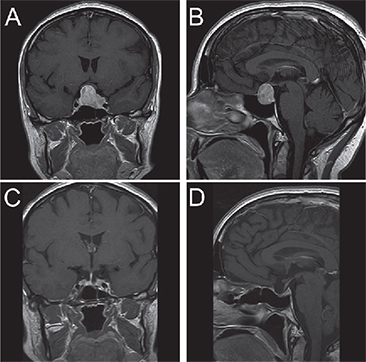

Un estudio de RM de silla turca evidenció un macroadenoma hipofisiario de 23 mm de diámetro mayor, con extensión supraselar, de modo que contactaba el quiasma óptico, e invadía el seno cavernoso izquierdo (Figura 1-A y B); sin embargo, la campimetría computarizada no mostró alteraciones.

La evolución post operatoria fue satisfactoria. A los 3 meses de operada se realizó RM que mostró pequeño remanente de tejido hipofisiario a izquierda, en relación con el seno cavernoso izquierdo (Figura 1-C y D).